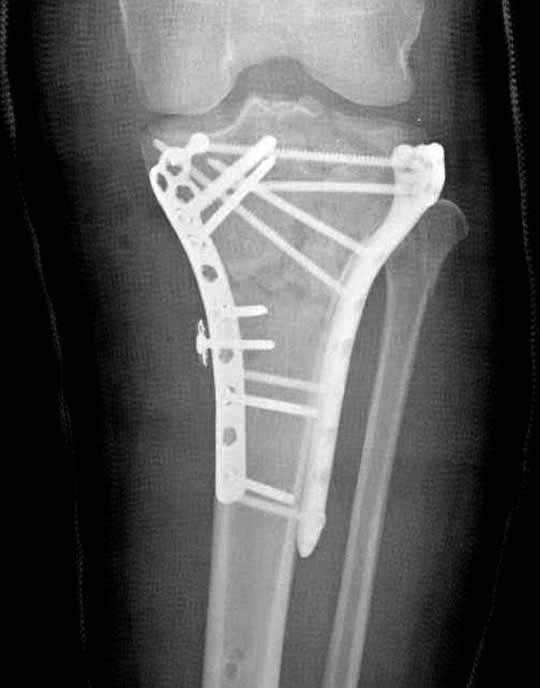

Частая ошибка, когда фиксацию двух колонного перелома проводят одиночной пластиной, т.е с одной стороны, и такая фиксация не удерживает, происходит вторичноое смещение. Необходимо нейтрализовать второй пластиной или дополнительным наружным фиксатором.

Если у вас, кроме пластины, нет другого альтернативного варианта, тогда, учитывая мягкотканые проблемы с наружной стороны, я бы рекомендовал операцию делать в два этапа. Преимущества, сперва репозиция и фиксация перелома с медиальной стороны, а затем, после улучшения состояния мягких тканей, зафиксировать с латеральной стороны. Современные пластины имеют латеральный Jig для перкутанных мини доступов.

В приложении этапы фиксации Both Column Fx и пластиной Synthes для плеча при переломе медиального мыщелка.

Был бы очень признателен Александру Челнокову за предоставление методички..... Коллеги, спасибо за советы... К сожалению томографа в больнице нет. Рассматривали вариант штифтования данного перелома, но большинство коллег против, да и опыта штифтования подобных переломов тоже нет. Если есть рентгенограммы заштифтованных подобных переломов, коллеги, выложите на обозрение, пожалуйста….Долго искали и все же остановили пока свой выбор на проксимальной медиальной большеберцовой пластине Numelock фирмы Страйкер.